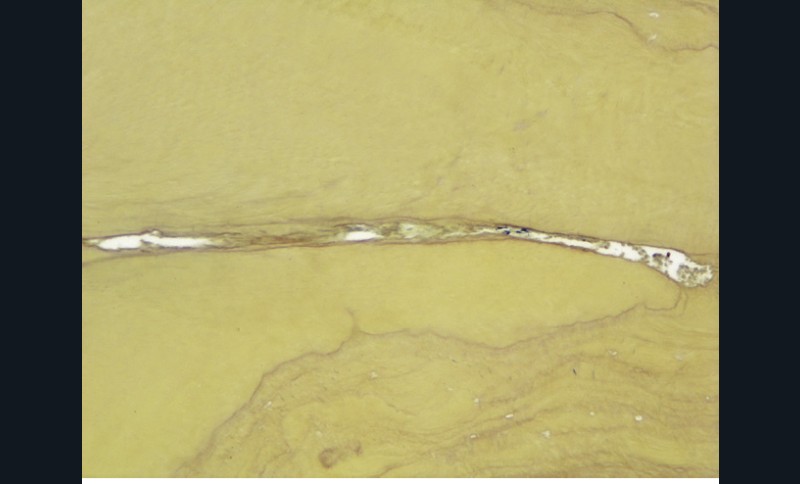

Si l’étude de Peters [18] nous montre que l’instrumentation laisse 35 % du volume canalaire non instrumenté, Ricucci et Siqueira montrent que la préparation physico-chimique n’élimine que partiellement les tissus nécrotiques à l’entrée des canaux latéraux, des isthmes et des ramifications apicales, en laissant des tissus enflammés et infectés, en association avec des lésions apicales [29] (fig. 4 et 5).

Fig. 4 – Coupe d’une racine mésiale de molaire mandibulaire avec deux canaux traités. Coupe à 3 mm de l’apex, coloration Brown et Brenn, technique modifiée par Taylor. Ces images montrent un isthme étroit avec une infection bactérienne, ce qui prouve l’importance de désinfecter et d’inclure l’isthme dans les traitements conventionnels et dans les rétropréparations apicales en chirurgie endodontique.